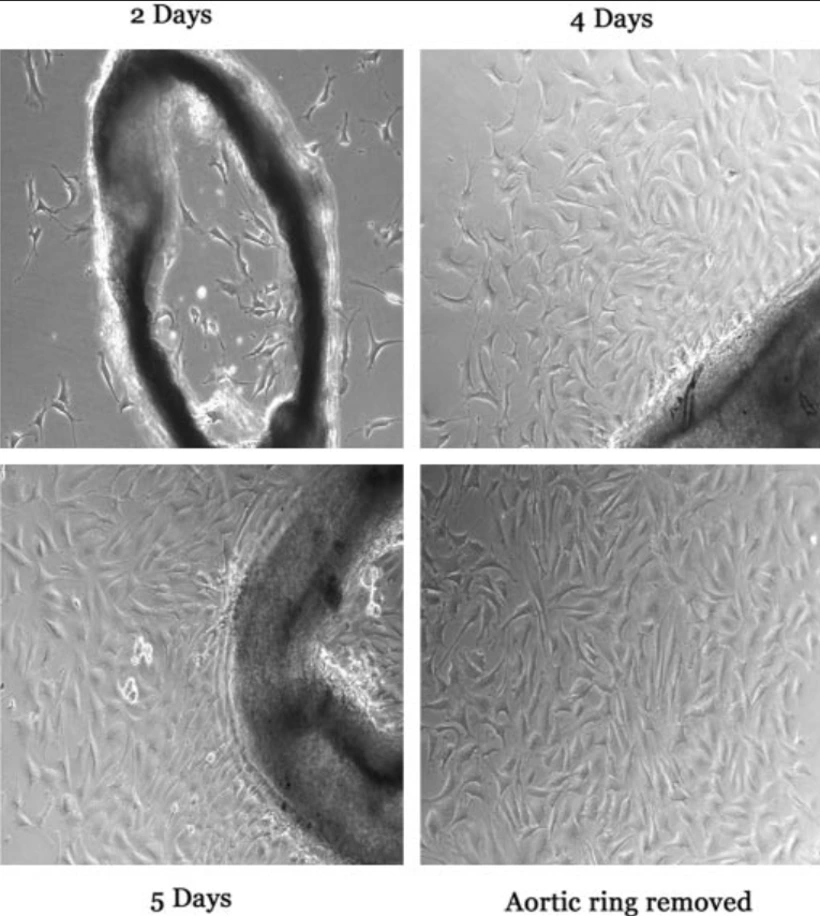

BALB/c Mouse Aortic Endothelial Cells (MOEA) are primary endothelial cells that are isolated from the aorta of BALB/c mice and are commonly used as an in vitro model that is physiologically relevant and genetically well-defined for studying vascular endothelial biology. MOEA cells display the classic cobblestone morphology of endothelial monolayers and express characteristic endothelial markers, such as CD31 (PECAM-1), VE-cadherin, von Willebrand factor (vWF), and endothelial nitric oxide synthase (eNOS), indicating their vascular identity and phenotype.

MOEA cells are functionally significant for modeling vascular homeostasis, angiogenesis, inflammation, and endothelial barrier function. They are responsive to various stimuli, including pro-inflammatory cytokines, shear stress, and hypoxic conditions, and are thus well-suited for studying endothelial activation, leukocyte adhesion, oxidative stress, and nitric oxide signaling. These cells are also commonly used in research related to atherosclerosis, vascular remodeling, thrombosis, and metabolic or immune-mediated vascular diseases.